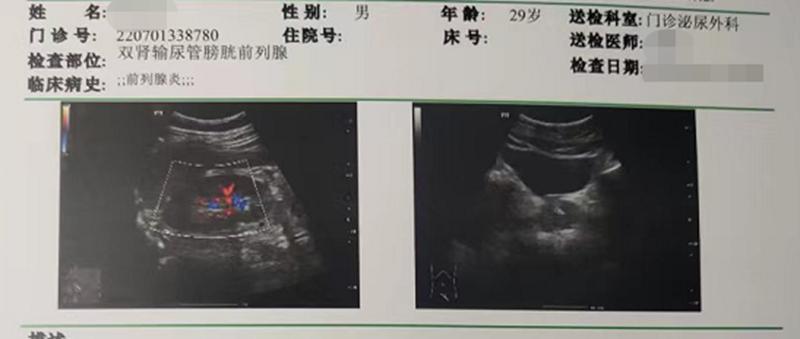

王先生第一个疗程前的前列腺B超检查单:前列腺形态正常,轮廓清晰,实质回声欠均匀,呈细小点状回声,大小约:39.4*29.4*24.7mm*mm*mm,其中可数个别强回声光点,较大约6.5*3.4mm,后未见声影。

王先生第二个疗程后的前列腺B超检查单:前列腺前后径约2.8cm,左右径约3.9 cm,上下径约3.0 cm,实质内查见点片状强回声。